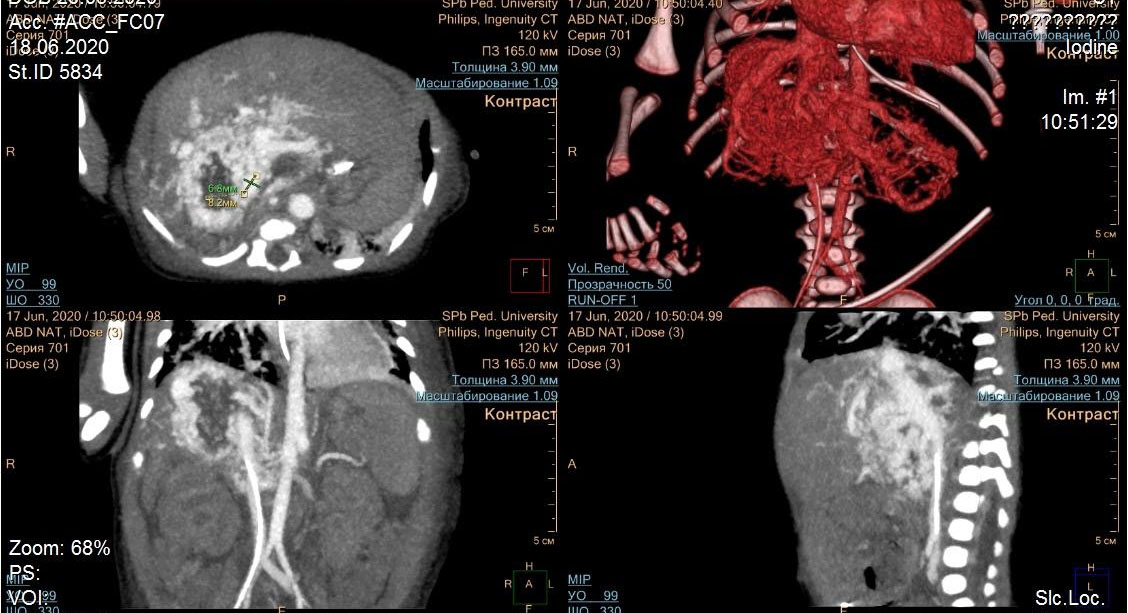

Дыхательная и сердечная недостаточность у младенца из Калининграда развились на следующий день после рождения. Врачи, выполнив компьютерную томографию, заметили у ребёнка признаки неправильного соединения артерий и вен печени. Специалисты называют такое состояние сосудистой мальформацией. Пациента срочно доставили в отделение реанимации клиники СПбГПМУ. Медики тщательно исследовали крупное образование печени. Стало очевидным, что без операции не обойтись.

– Врожденные гиперваскулярные новообразования и артериовенозные мальформации печени встречаются крайне редко. В мировой литературе имеются единичные описания этой патологии. При этом летальность варьирует от 30 до 80%, – рассказал заведующий отделением рентгенохирургических методов диагностики и лечения Педиатрического университета Михаил Комиссаров.

Он также пояснил, что из-за аномального соединения артерий и вен у таких пациентов ухудшается кровоснабжение органов и тканей, расположенных ниже поражённого участка. Нагрузка на сердце и легкие возрастает, в связи с чем, и развивается сердечно-лёгочная недостаточность.

– Так как объем патологических тканей у ребёнка был очень большим, удалить их рутинным хирургическим методом не представлялось возможным, – рассказал Михаил Комиссаров и добавил: «таким пациентам показана рентгенэндоваскулярная операция. Это когда через бедренную артерию заводят очень маленький катетер непосредственно в сосуды печени, которые питают мальформацию, и перекрывают их».